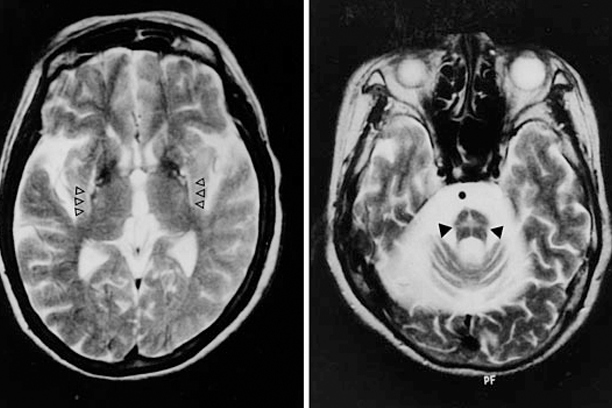

- Parkinson’s disease affects the nerve cells in the substantia nigra of the brain that produce dopamine- a neurotransmitter messenger in the body that allows smooth co-ordinated movements.

- When a person has Parkinson’s disease, these dopamine producing cells start to degenerate and amount of dopamine produced in the brain decreases. Messages from the brain telling the body how and when to move are delivered abnormally, leaving a person incapable of initiating and controlling movements in a normal way.

- It is characterized by loss of approximately 60-80% of the dopamine producing neurons in substantia nigra before the motor symptoms appear, and a profound loss of dopamine in striatum.

There is no single test that can diagnose your Parkinson’s disease. The diagnosis is mainly done by history and clinical examination of typical symptoms (described above) by your Parkinson’s disease and Movement Disorders Specialist. In the early stage of the disease, it may be difficult to differentiate between Parkinson’s disease and atypical parkinsonian syndromes due to mild and overlapping symptoms. As the symptoms gradually progress, the diagnosis becomes more obvious. Brain MRI often helps in differentiating PD from atypical parkinsonism.